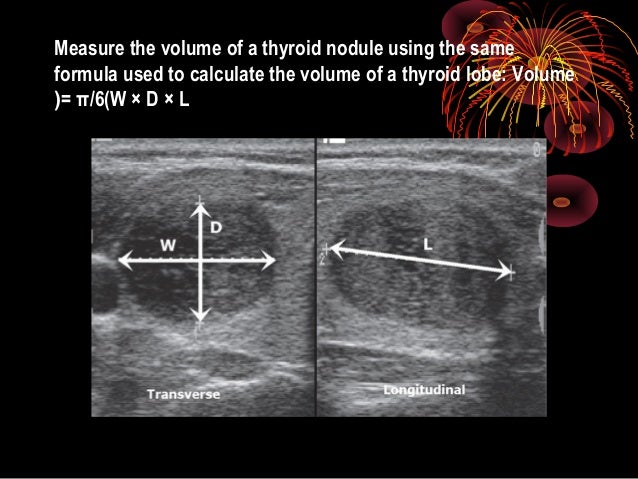

How To Measure Thyroid On Ultrasound Length Width AP Depth Volume